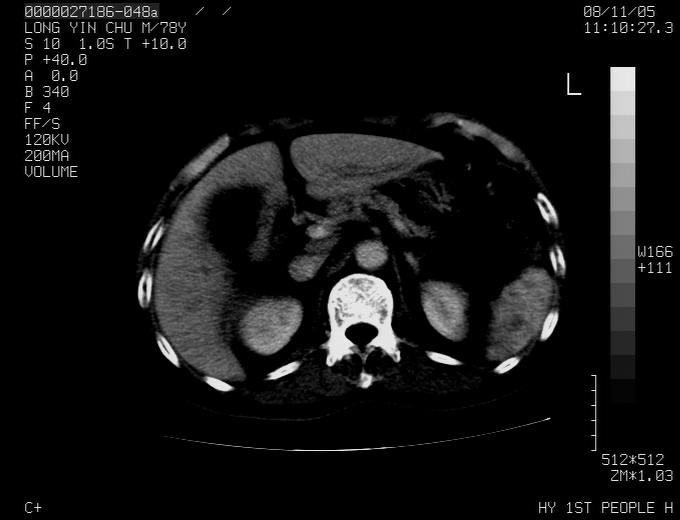

标题: CT16532:M78Y,肝脏病变,请会诊 [打印本页]

标题: CT16532:M78Y,肝脏病变,请会诊

腹胀,腹痛就诊,男性,78岁,外院b超未见异常。

肝ca,脾肾转移

支持脾肾转移瘤,双侧胸腔积液。

考虑弥漫性肝癌并脾及双肾转移.双侧胸水.

图片质量欠佳:多考虑:左侧肾癌。脾脏转移!胸膜转移!

肝脾肾转移瘤可能性大,左肾不除外梗塞,双侧胸水

考虑弥漫性肝癌并脾及双肾转移,双侧胸水。

考虑肝癌并双肾及脾脏转移;双侧胸腔积液。